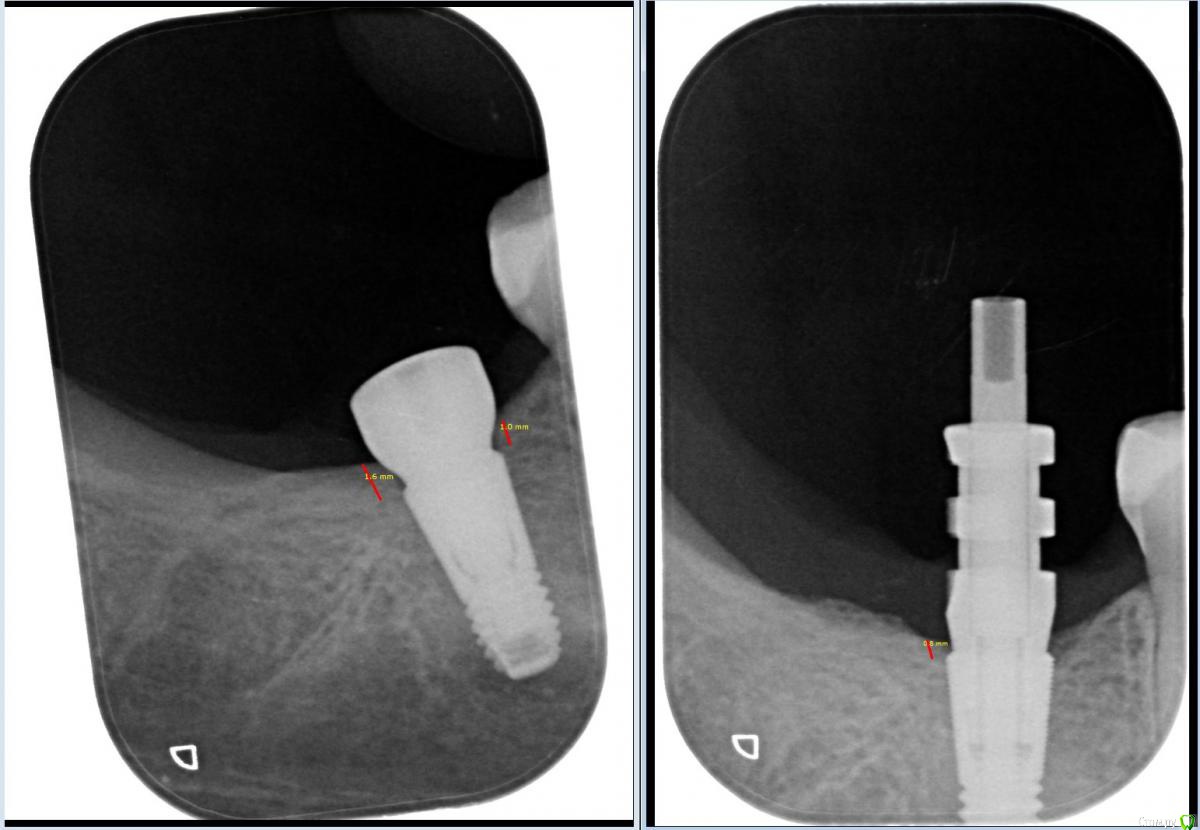

колесников Опубликовано 25 сентября, 2016 Поделиться Опубликовано 25 сентября, 2016 Наглядный пример почему немедленная имплантация предпочтительнее отсроченной ,а одно этапная лучше двух этапной и почему приходится применять субкрестальную постановку даже у систем с полированной шейкой. Между снимками 2 месяца. Пациентка была заимплантирована спустя 6 месяцев после атипичного удаления (стороннего). Широкого отслаивания не производилось,разрез только по гребню и ролл-смещение лоскута вестибулярно. Формирователь сразу. Течение безсимптомное. Гигиена идеальная.Итого: 1 разрез =потери практически 1мм кости. Ссылка на комментарий

колесников Опубликовано 26 сентября, 2016 Автор Поделиться Опубликовано 26 сентября, 2016 (изменено) Кость уходит по гребню при скелетировании-это не мной доказано,но подтверждено этим частным случаем и потому приходится применять субкрестальную постановку даже у систем с полированной шейкой (предполагающих крестальную или супракрестальную постановку) с расчётом на эту убыль. Нельзя сказать что причиной убыли стал формирователь,т.к резорбция горизонтальная на всей площади отслаивания, а не краевая ,непосредственно у шейки фдм (на втором снимке ,на гребне дистально, видны некие "пузыри"- это то что осталось от некогда однородного слоя костной ткани и эта зона с фдм не контактирует). На сколько была бы потеря больше при двух этапном подходе? Думаю в 2 раза больше. Изменено 26 сентября, 2016 пользователем колесников Ссылка на комментарий

колесников Опубликовано 27 сентября, 2016 Автор Поделиться Опубликовано 27 сентября, 2016 Я, например, считаю, что кость в данном месте ушла из-за слишком близкого расположения формирователя.Но в участке дистальнее импланта она также ушла,а контакта в формирователем там нет. А медиальнее не ушла. Потому что у 6ки я не отслаивал,обошёл сосочек,а дистальнее отслаивал перекинув лоскут.Авторские заявления не голословны. Тот же Ж.Кюри показывал результаты костной пластики и соответственно объём резорбции начиная с 1996г . Ключевой вывод : первоначально достигнутый результат может быть утрачен в среднем на 20-30% при последующем скелетировании. И.Гамборена показывал 5-9 летние результаты. Ключевой вывод:случаи с одномоментной имплантацией более предсказуемы в плане объёма резорбции кости в сравнении с отсроченой. Ссылка на комментарий